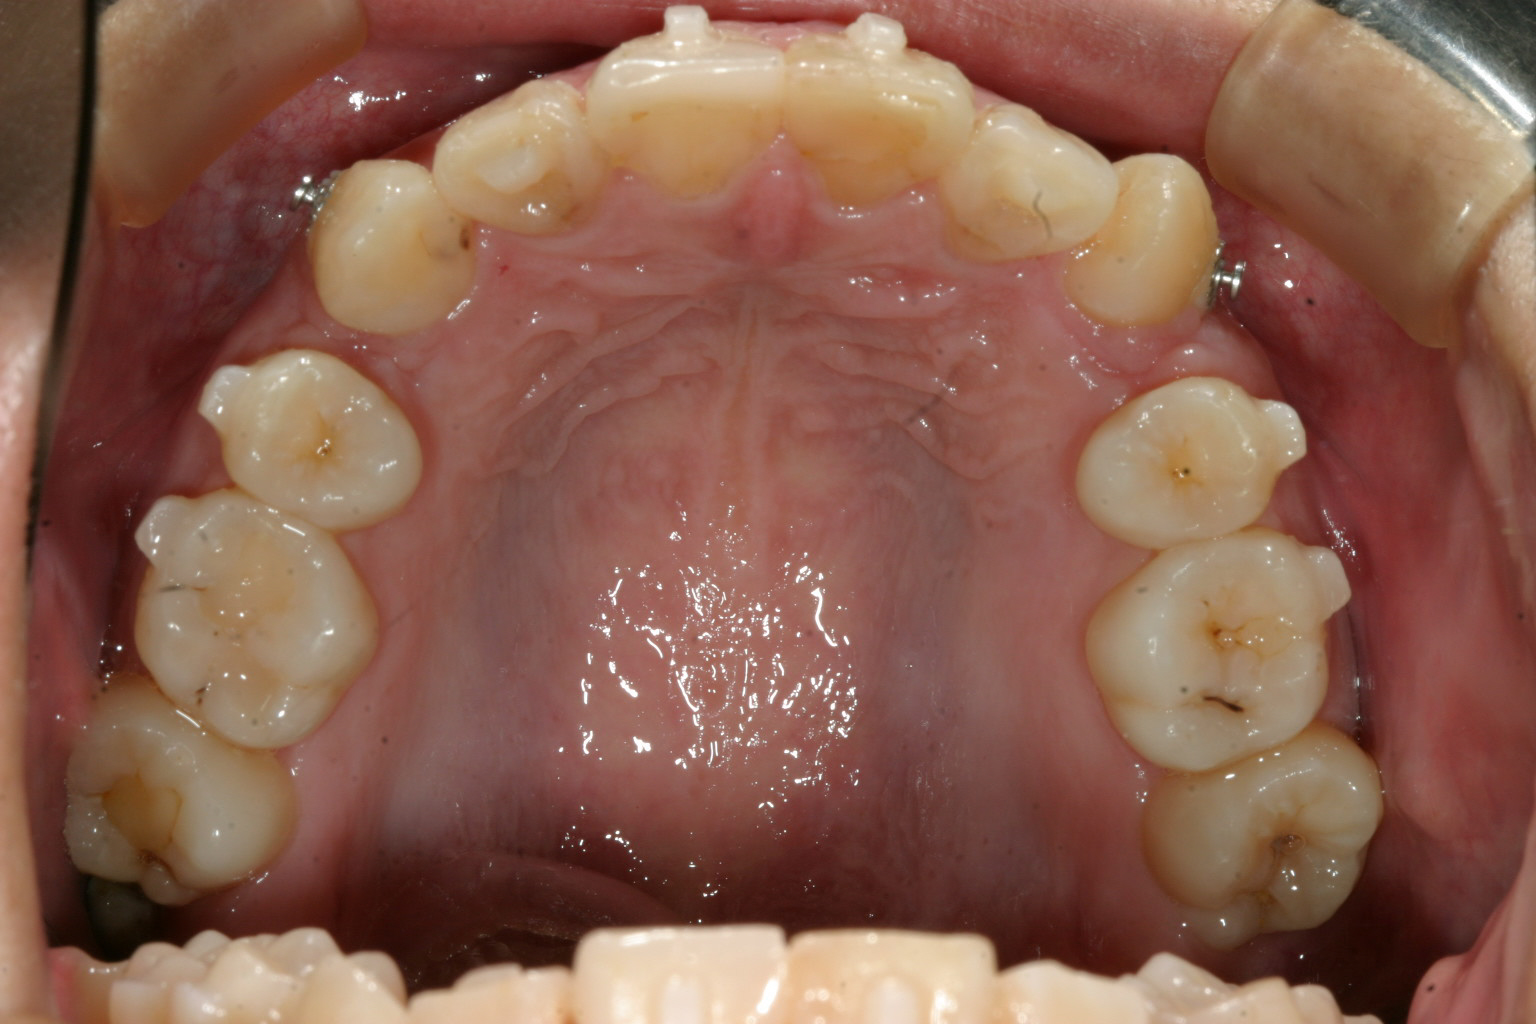

インビザライン開始後7か月後の状態です。 アタッチメントが付いているのが確認できます。 犬歯がだいぶ歯列に乗ってきてますがまだまだです。 この状態のときに犬歯にアップダウンエラスティックを使用し更にアーチ内に引き込みます。

左右上顎の小臼歯を抜歯して改善致しましたケースです。 綺麗に並んでます。